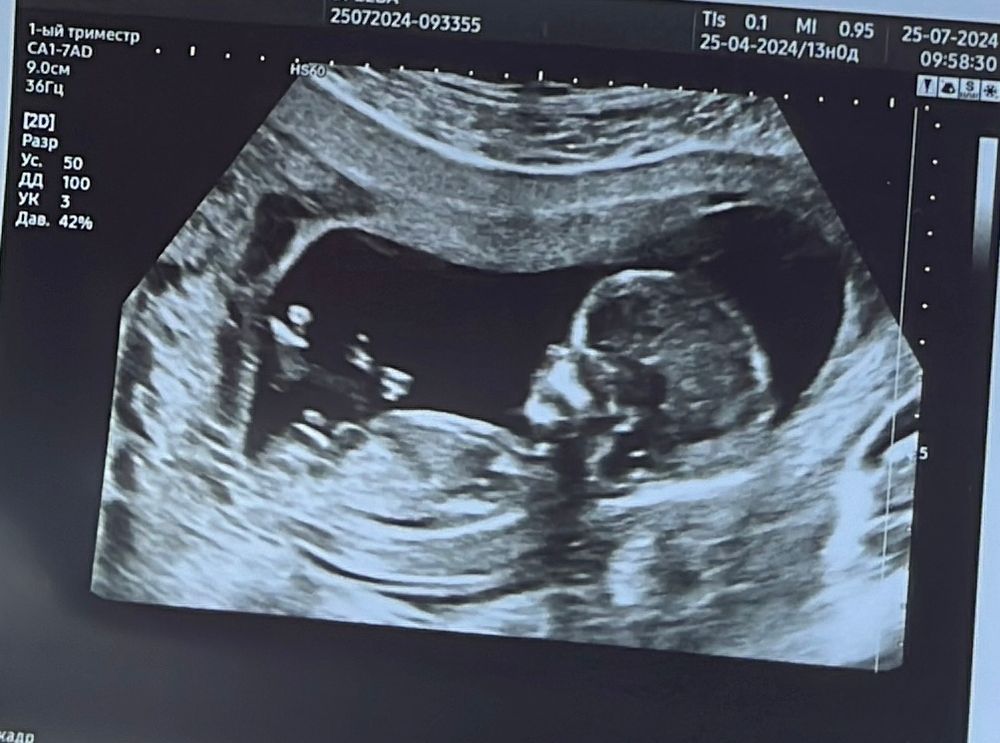

Katiii в Благополучная беременность год Мальчик или девочка как думаете? Анализы, скрининги Как думаете мальчик или девочка? Посмотрите еще 20 записей на эту тему Отменить Ответить Katiii Пусть будет девочка ☺️ 25.07.2024 Ответить Алиса Девочка 🩷 25.07.2024 Ответить Святая инквизиция Не видно, не гадайте) 25.07.2024 Ответить J Sha Мне кажется там писюн) 25.07.2024 Ответить Куку Девочка 25.07.2024 Ответить Sherry Мне кажется мальчик, с девочкой обычно бугорок прям параллельно с позвоночником☺️ 25.07.2024 Ответить Айгулька Девочка 25.07.2024 Ответить Юлия * Девочка 25.07.2024 Ответить Александра Мне тоже кажется, что девочка 25.07.2024 Ответить Ренка Мне кажется девочка) 25.07.2024 Ответить АМГ: между результатами 3 года и 1 беременность Перелет при отслойке плодного яйца Чаты Беременных Выберите чат: Январята-2026 Февралята-2026 Мартята-2026 Апрелята-2026 Майчата-2026 Июнята-2026 Июлята-2026 Августята-2026